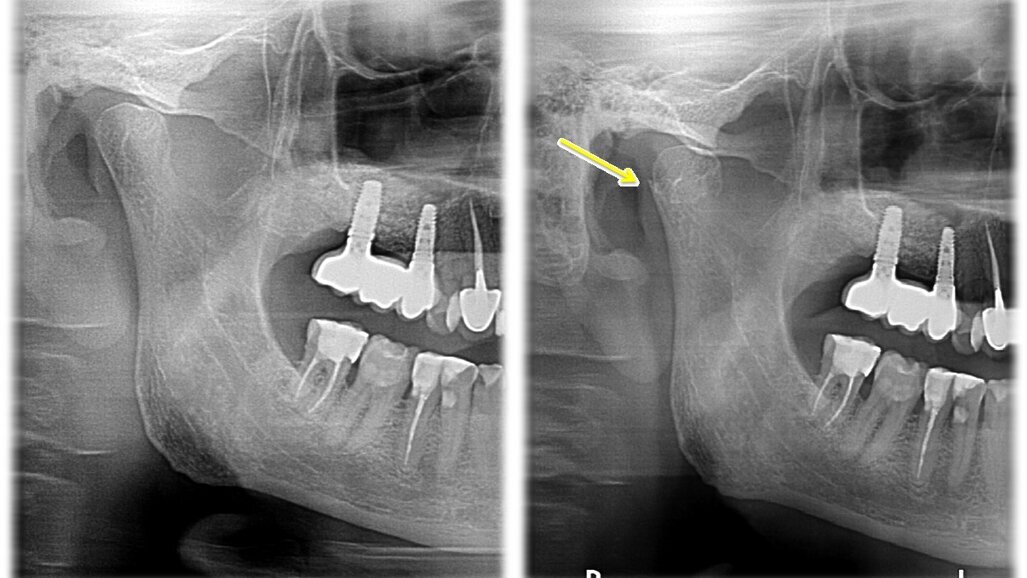

Zdjęcie panoramiczne w tym przypadku nie stanowiło jednoznacznej metody diagnostycznej. Dopiero, porównując zdjęcie po urazie ze zdjęciem wykonanym przed urazem, widoczne było skrócenie gałęzi żuchwy po stronie prawej. Dzięki wykorzystaniu przekrojów osiowych i transsektalnych w badaniu tomografem stożkowym o zmiennym polu obrazowania ustalono przyczynę zaburzeń okluzji u pacjenta oraz w sposób jednoznaczny określono uszkodzenie w obrębie stawu skroniowo-żuchwowego. Po analizie zdjęcia tomograficznego zdiagnozowano u pacjenta złamanie wyrostka kłykciowego żuchwy po stronie prawej. Co istotne, diagnostyka przeprowadzona na podstawie zdjęcia pantomograficznego nie dawało tak ewidentnego wyniku, jak obrazowanie stawu skroniowo-żuchwowego z wykorzystaniem obrazowania 3D. Bez porównania zdjęcia panoramicznego przed i po urazie dostrzeżenie nieprawidłowości było trudne dla niedoświadczonego lekarza.

Ryc. 4_ Zdjęcie pantomograficzne przed urazem (po lewo) i po urazie (po prawo).

Ryc. 7_Tomografia stożkowa o zmiennym polu obrazowania – stan po urazie i po zaopatrzeniu chirurgicznym złamania.